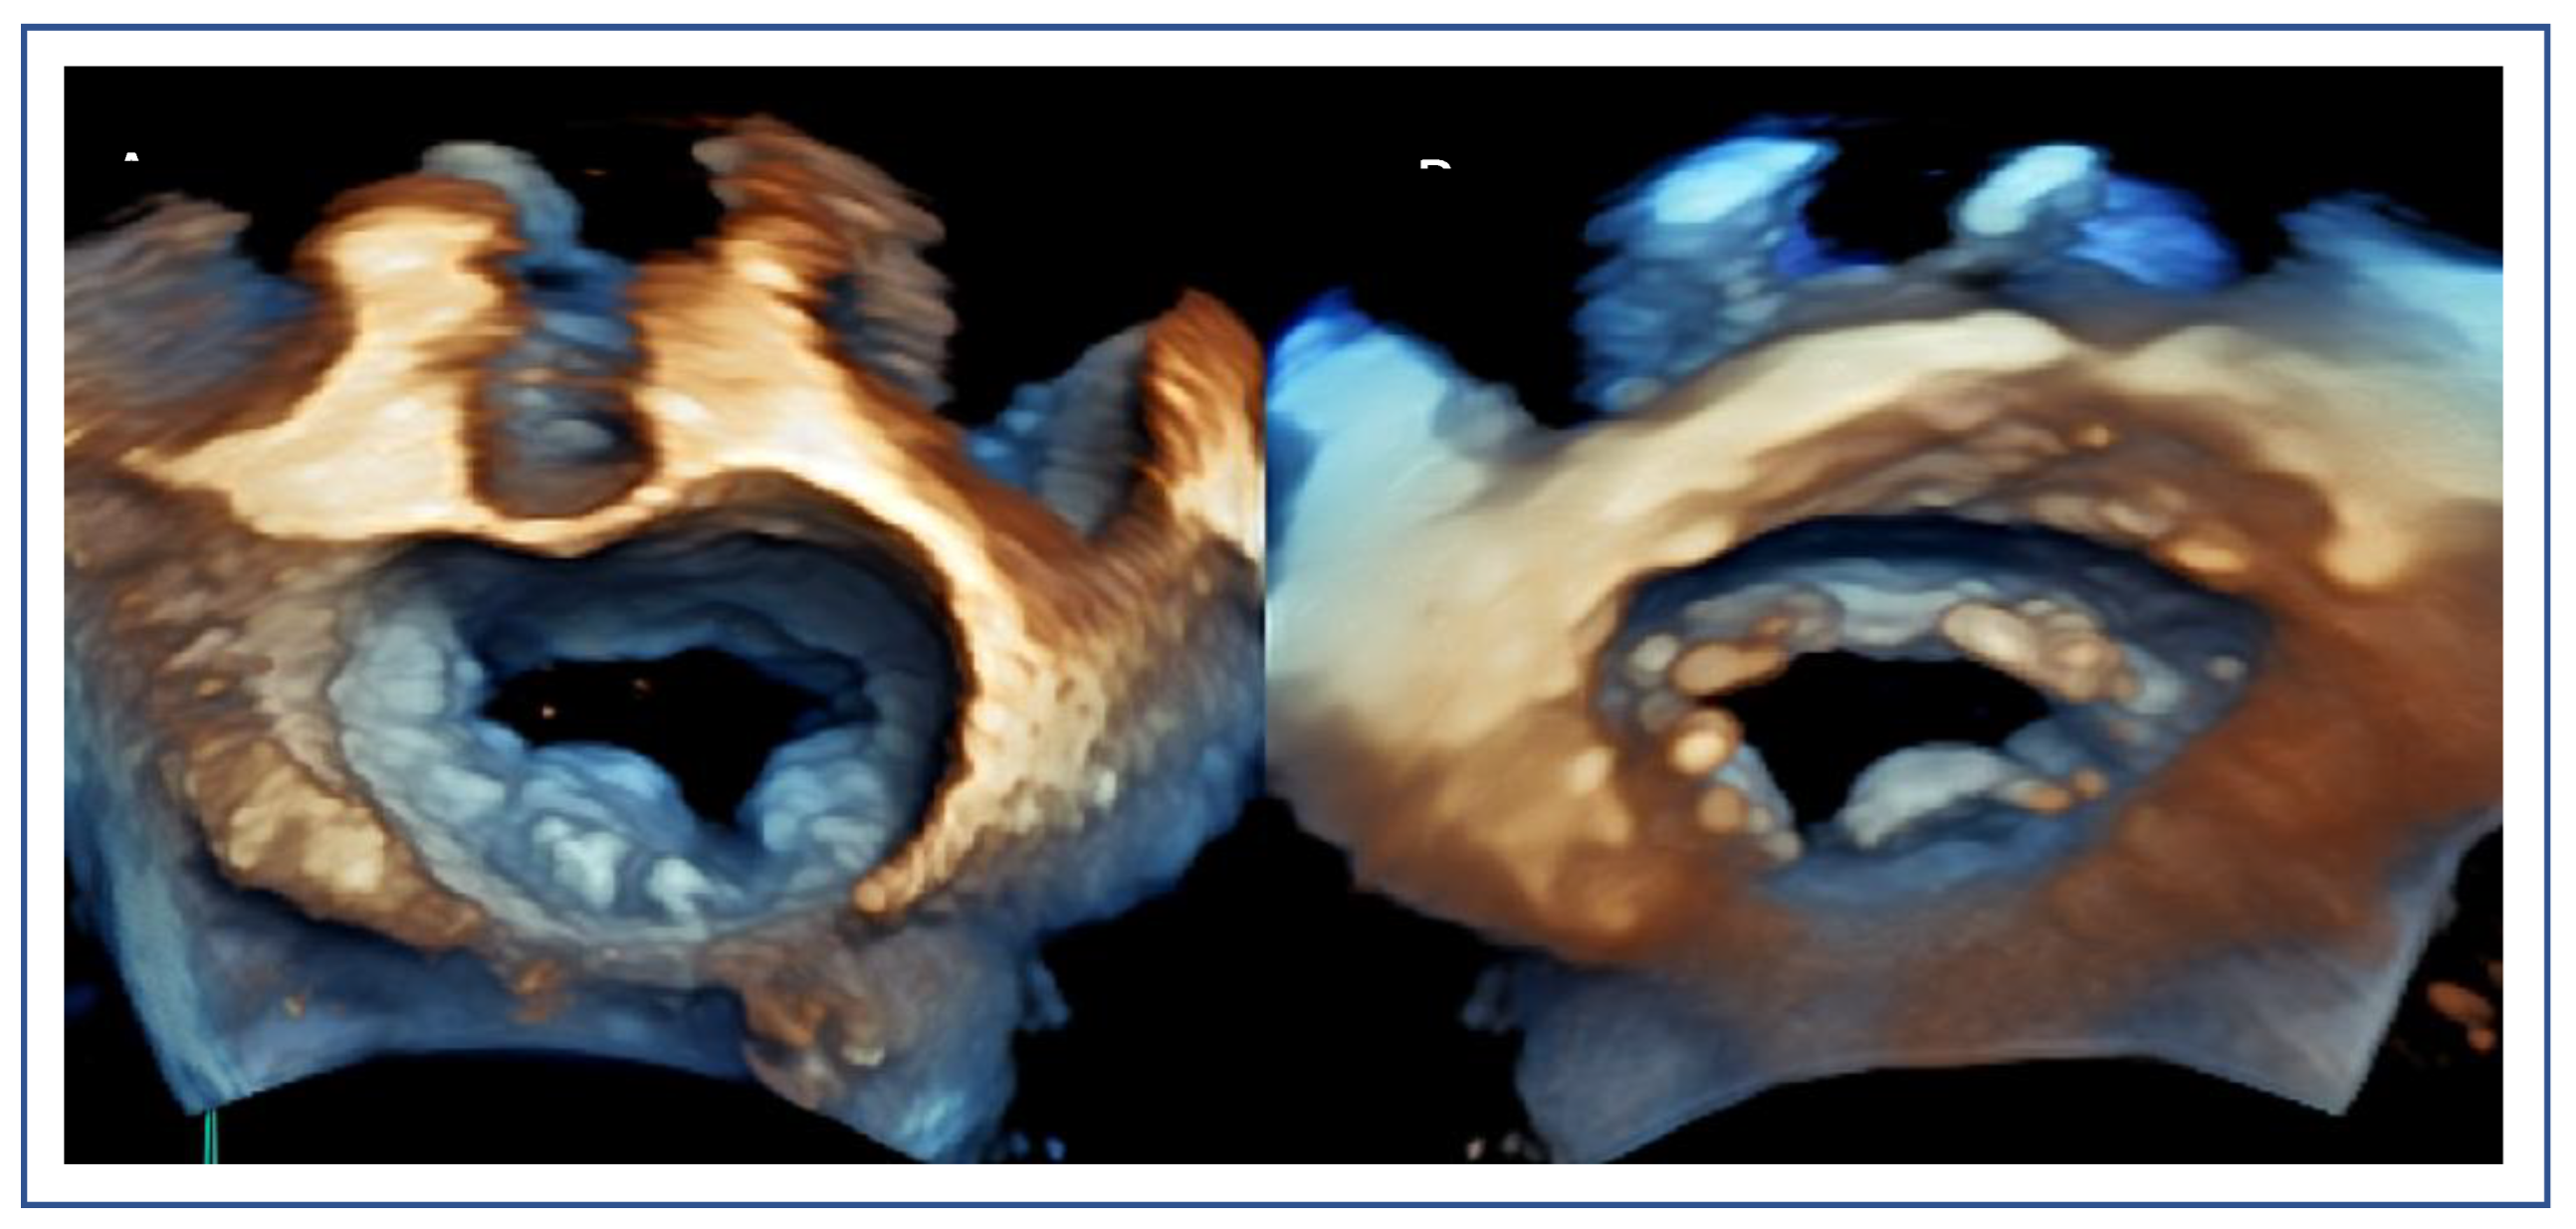

Posterior Leaflet Cleft-like IndentationThe posterior leaflet normally has two indentations that differentiate the scallops. A cleft-like indentation is defined as having a depth of at least 50% of the adjacent scallops [37,38] and 3D imaging is the best option to recognize such abnormalities (Figure 9). This feature makes grasping challenging and may lead to residual mitral regurgitation (MR).